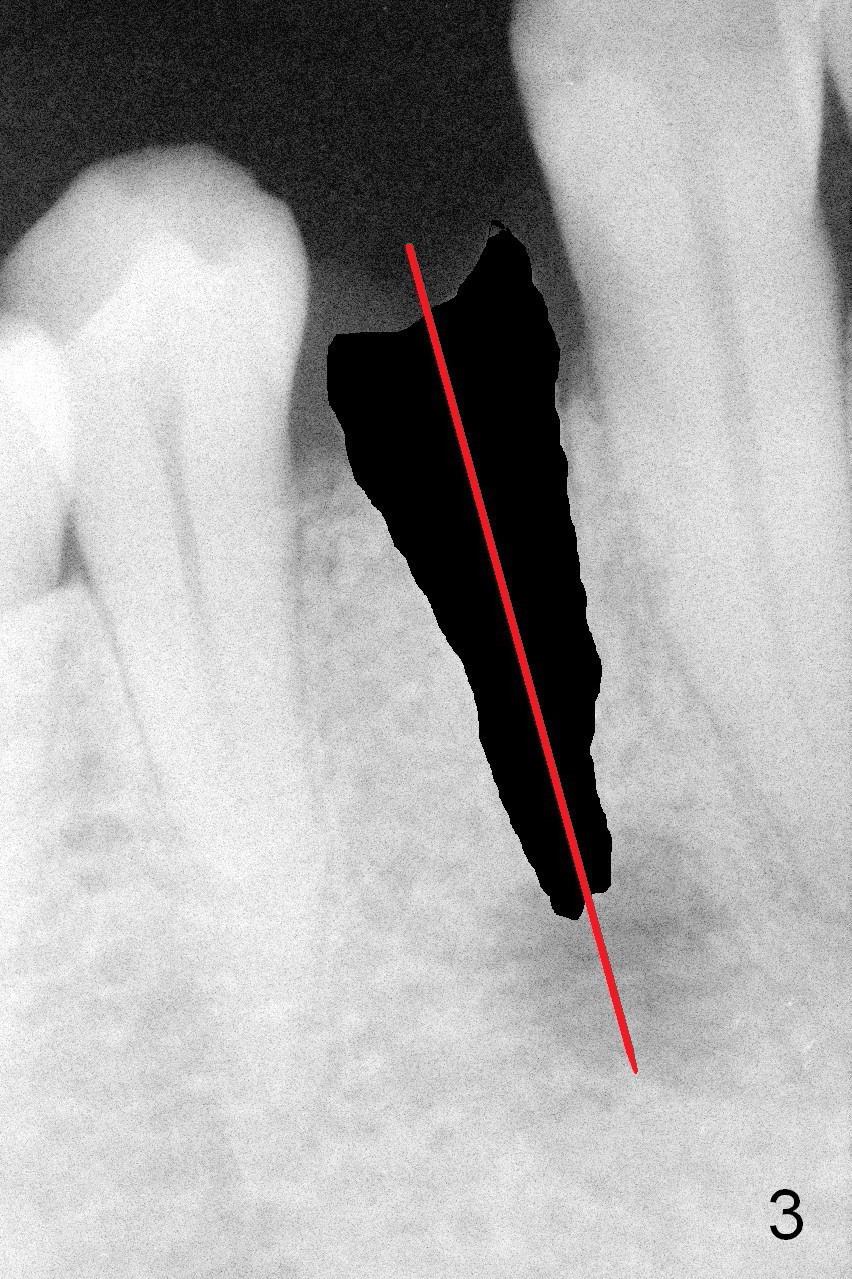

A 54-year-old man develops acute apical periodontitis associated with the tooth #28 (Fig.1). The latter appears to be non-salvageable with large periapical radiolucency (*). A 4.5x14 mm bone-level implant will be placed (Fig.2). The depth of osteotomy is to be tightly controlled after extraction (Fig.3 red long arrow) to avoid damage to the possible double Mental Loops (Fig.2 red dashed lines, 17 mm from the gingival margin). If the insertion torque is high, an immediate provisional is going to be fabricated. Bone graft is expected.